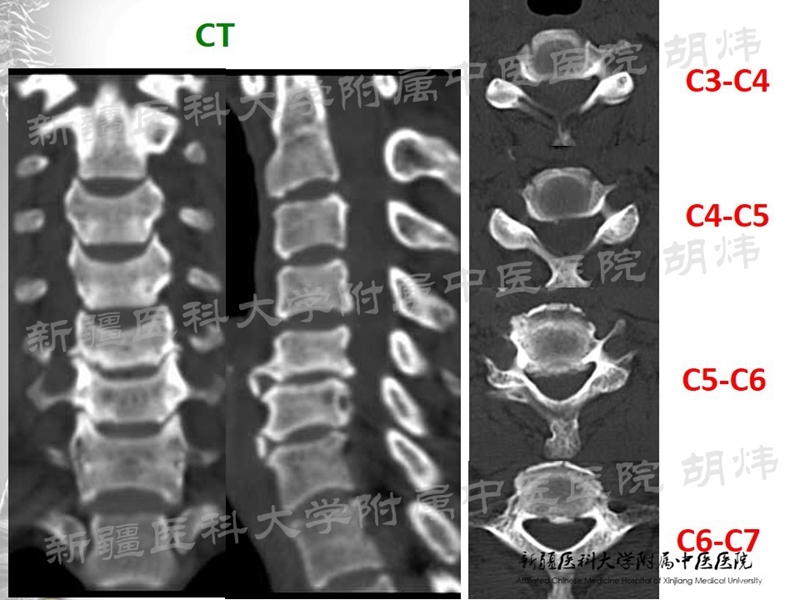

典型病例分享

(手术视频)